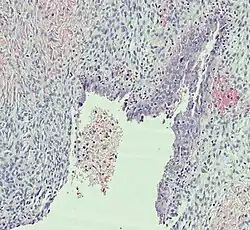

Histopathology

In case an ovarian cyst is surgically removed, a more definite diagnosis can be made by histopathology:

| Type | Subtype | Typical microscopy findings | Image |

| Functional cyst | Follicular cyst |

|

| Cystadenoma | Serous cystadenoma | Cyst lining consisting of a simple epithelium, whose cells may be either:[26]